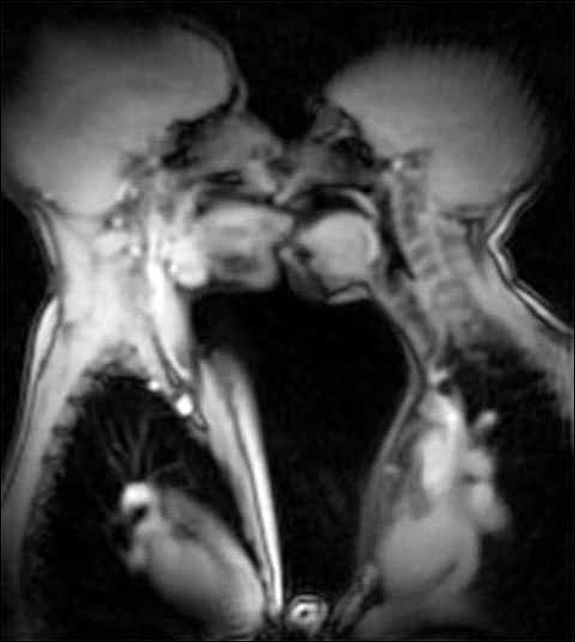

Врачи использовали эти сканеры, чтобы выявить, что происходит внутри человеческих ртов во вовремя поцелуя. Видео под названием "Анатомия поцелуев и любви в МРТ-сканере" было загружено интернет-пользователем на видеохостинг YouTube. В описании к ролику указано, что видео является первым французским поцелуем, совершенным под МРТ-сканером. Он был заснят с напряженностью поля в 3 Тесла.

Клип показывает движение языка во рту другого человека, а также сердца обоих участников, которые начинают биться быстрее.